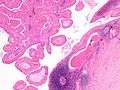

Histopathology of Warthin tumor in the parotid gland. Another view of a file "Warthin tumor (1).jpg". H&E stain.